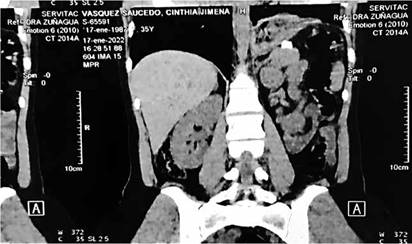

Cuenta con exámenes imagenologicos: Serie contrastada esófago gastroduodenal: se observa ascenso de fondo gástrico por encima del margen diafragmático izquierdo (FIGURA 1). TAC toracoabdominal contrastada donde evidencia elevación diafragmática con retracción hacia caja torácica izquierda de fondo gástrico (FIGURA 2). Además, cuenta con laboratorios sanguíneos alterados (TABLA 1).

FIGURA 2: TAC toracoabdominal contrastada